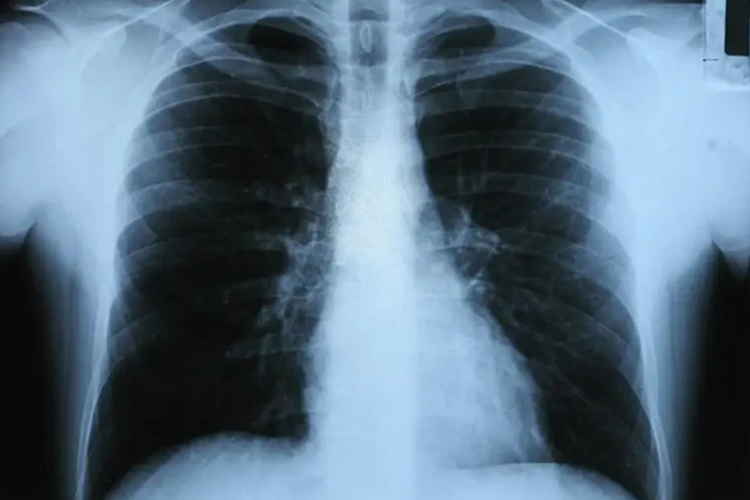

肺结核患者通过X线检查可发现肺部病变处呈多状态,即浸润增殖、干酪、纤维钙化病变可同时存在,密度不均匀边缘较清楚和病变变化较慢,易形成空洞和播散病灶。正常人群肺部X线多无异常。